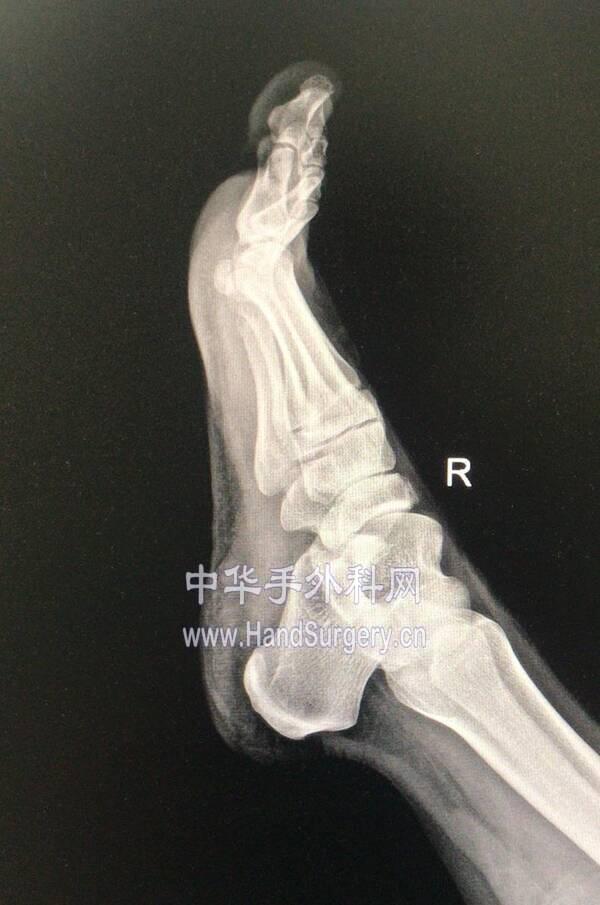

微信图片编辑_20191218175444.jpg 微信图片编辑_20191218175548.jpg

微信图片编辑_20191218175511.jpg 微信图片编辑_20191218175530.jpg

微信图片编辑_20191218175444.jpg 两侧均为中度

微信图片编辑_20191218175511.jpg